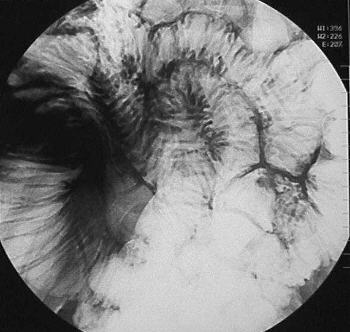

X-RAY

Coeliac Disease

Enteroscopy > Push Enteroscopy > Coeliac disease